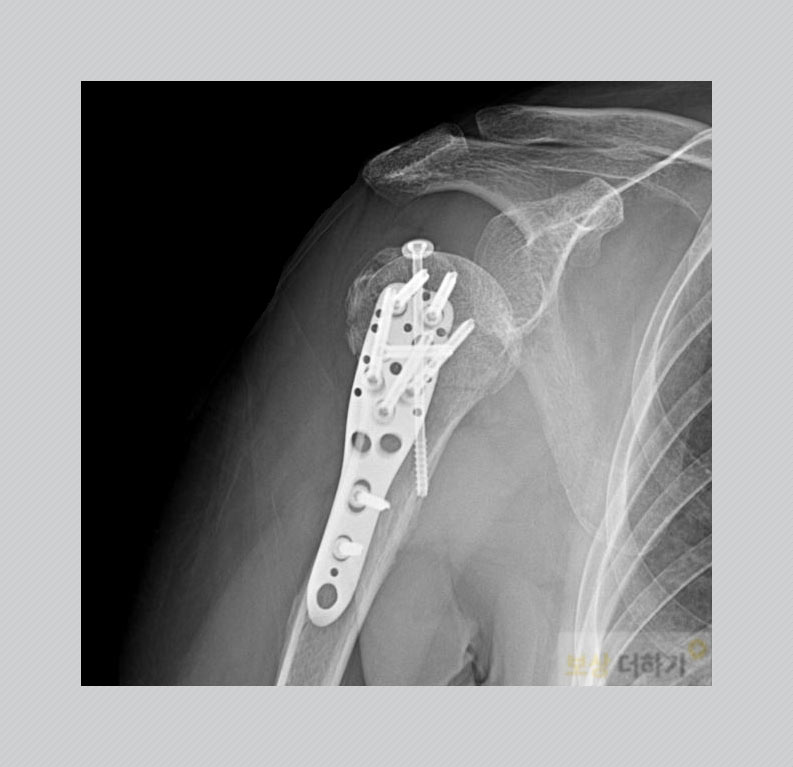

다음과 같이 뼈가 잘 붙을 수 있는 위치로 정복을 한 후 고정을 해주는 수술을 시행 받았습니다. 수술 후에는 정기적으로 내원하여 유합이 잘 되는지 확인을 받으셨고, 물리치료와 재활운동을 병행하며 어깨 관절의 운동 범위 회복을 위해 노력하셨습니다. ▽ 관혈적 정복술 및 내 고정술